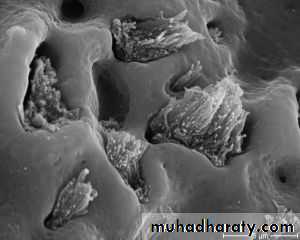

migration of osteoblasts & osteoid production to the implant surface

Last of approximately 1 month.

Osteophylic Phase

the bone cells spread along the implant surface laying down osteoid and takes about 3 months

Osteoconductive Phase